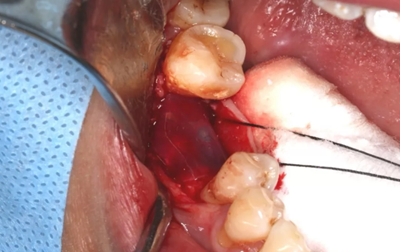

14、植骨手術(shù)過(guò)程

刮除肉芽組織及種植體表面清潔后,種植體唇側(cè)骨缺損區(qū)植入人工骨粉。

(攝于2017年8月10日)

引導(dǎo)骨再生